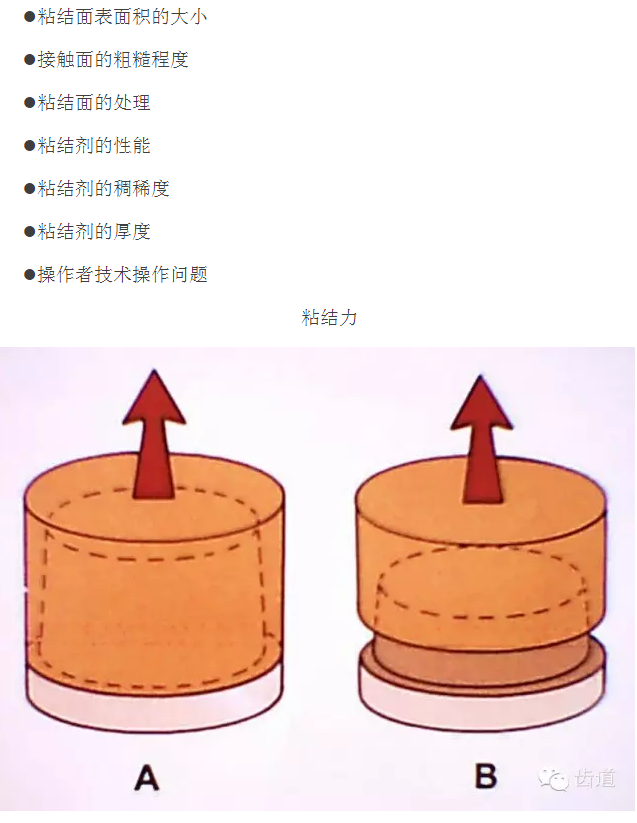

正壓力:即修復體的密貼程度(小于0.2mm)

表面粗糙程度